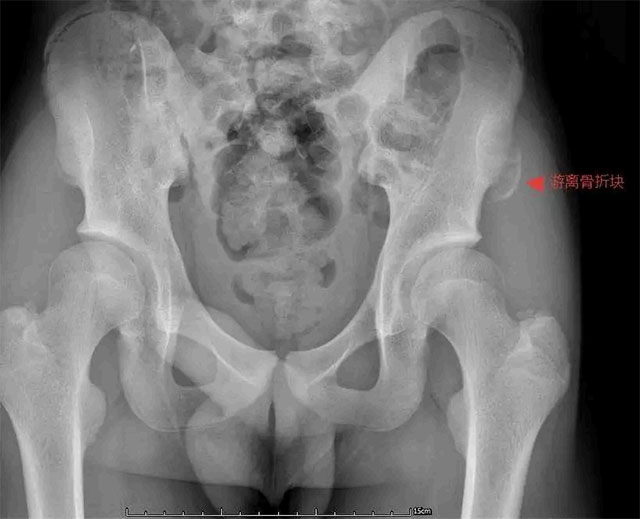

14岁的短跑主力小张,在校运会起跑训练中猛地蹬地发力,左髋部瞬间传来“撕裂般”剧痛,当场瘫坐跑道,冷汗浸透运动服。检查显示,他的左髂前上棘撕脱骨折,骨折块移位达3cm,正是起跑时肌肉的猛烈收缩牵拉导致了损伤。

16岁足球前锋小郑在友谊赛冲刺射门时,右脚发力的刹那右侧髋部钻心疼痛,无法站立,确诊骨折移位2.5cm,不得不暂别绿茵场。

15岁的小王在800米测试后半程突发左髋痛,步伐错乱,勉强冲过终点后弯腰、转身都困难,就医后发现骨折块移位2.2cm,一次常规测试竟引发骨折让他始料未及。

青少年骨骺尚未完全闭合,髂前上棘作为重要肌肉附着点,在短跑、跳跃等爆发性运动中,肌肉收缩的牵拉力一旦超过骨骺承受极限,易引发这种无碰撞的“隐形骨折”,这类损伤在青少年群体中并不少见。